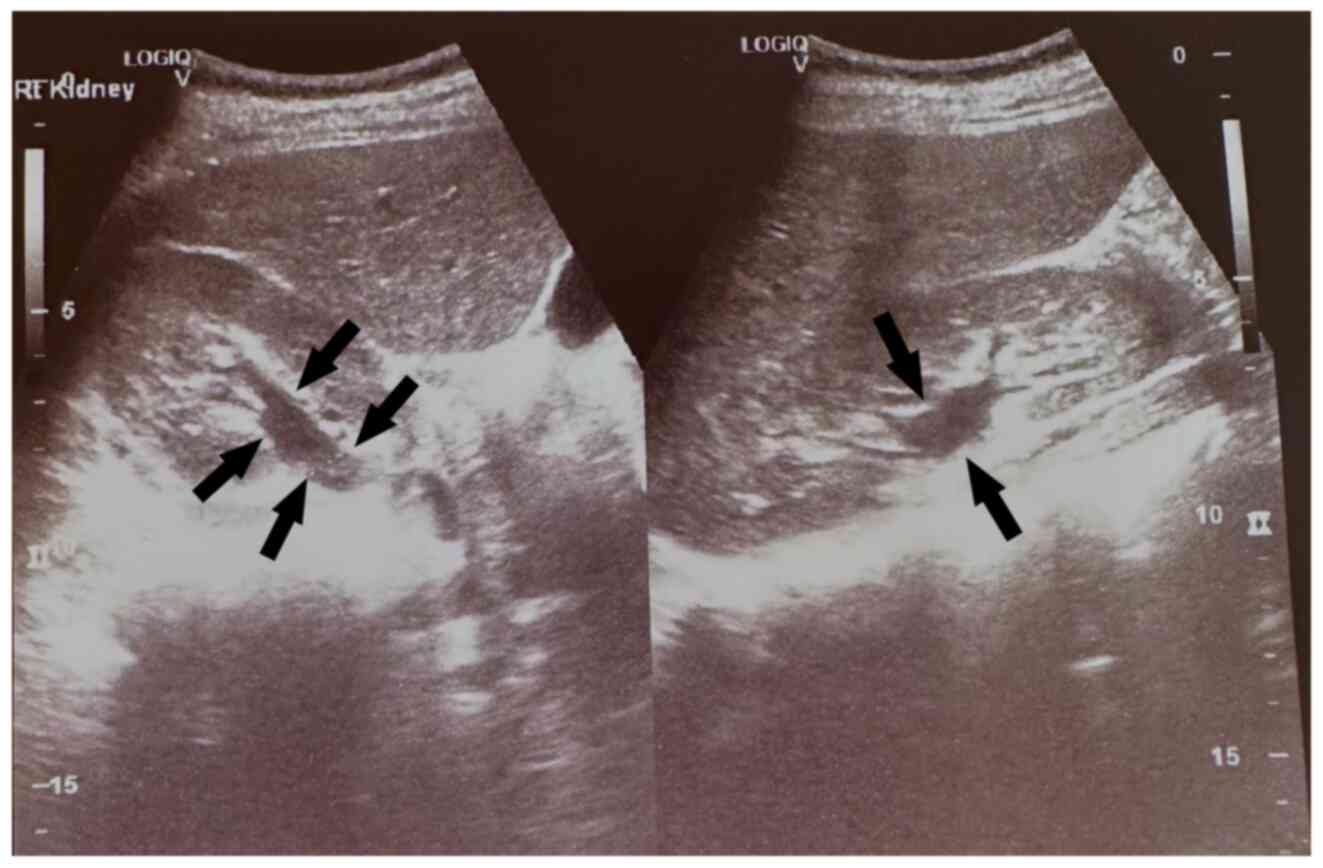

Large bladder flap haematoma following a caesarean section associated with right hydroureteronephrosis: A case report and a mini‑review of the literature

Post‑caesarean section bladder flap haematoma is a rare postpartum complication. There are currently no specific treatment protocols, at least to the best of our knowledge. In general, the failure of conservative treatment with antibiotics requires the re‑operation and surgical drainage of the haematoma. The present study describes the case of a primiparous pregnant woman who, at 40 weeks of pregnancy, delivered by caesarean section. On the 3rd post‑operative day, the puerperant, haemodynamically stable, developed febrile infection. During the evaluation, the presence of bladder flap haematoma associated with moderate right hydroureteronephrosis was found. The failure of conservative management led to the decision to perform a re‑laparotomy 1 week later. During the surgery, a large bladder flap haematoma was found with a retroperitoneal extension into the right parametrium. The surgical drainage of the haematoma and thorough haemostasis in the area of the vesicouterine pouch was performed. The patient was discharged from the clinic on the 5th post‑operative day following the re‑operation. After 2 weeks, an ultrasound revealed the complete repair of the lesions in the vesicouterine pouch and the right kidney. In the present study, a brief review of literature is also provided regarding the diagnostic and therapeutic management of patients with post‑caesarean section bladder flap hematoma.

Figure 2